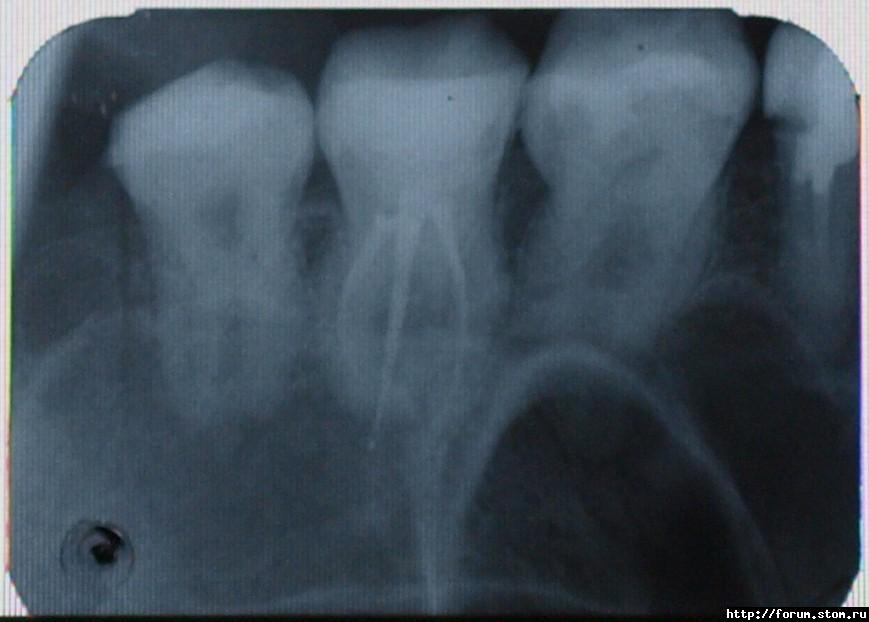

vitaly. Опубликовано 4 ноября, 2011 Поделиться Опубликовано 4 ноября, 2011 В районе шестерки, периодически немного ноет...какой зуб - не могу понять - то ли это сама шестерка, то ли это пролеченная семерка(лечили пульпит, каналы пломбировали, постоянная пломба с 13 октября 2011, был выход материала за канал...), то ли это пятерка(врач глядя на снимок узрел что-то...Что делать? Снимок прилагаю. Ссылка на комментарий

Stomart Опубликовано 5 ноября, 2011 Поделиться Опубликовано 5 ноября, 2011 Перед сном ноет, особенно если горизонтальное положение, когда сажусь - менее выражен болевой синдором, ... Похоже на пульпит (воспаление нерва). Сходите к доктору, пусть хорошенько обследует шестой зуб. Ссылка на комментарий

vitaly. Опубликовано 7 ноября, 2011 Автор Поделиться Опубликовано 7 ноября, 2011 (изменено) Сходил сегодня, он посмотрел и внешне ничего не обнаружил...сказал, что просто возможно я застудился немного(хотя вроде никаких признаков простуды у меня и нет помине!) Да,кстати, с утра вокруг этого зуба я обнаружил покраснение...Скажите а для диагностики пульпита достаточно рентгеновского снимка и внешнего осмотра? а может быть под старой пломбой пульпит не диагностируемый данными средствами? Изменено 7 ноября, 2011 пользователем vitaly. Ссылка на комментарий